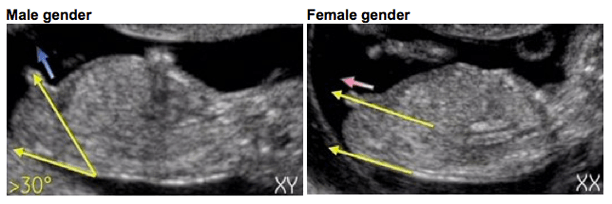

And that, my friends, is where I learned about the Genital Tubercle Angle or… the Angle of the Dangle.

So, basically, by about 12 weeks into your pregnancy, the baby’s genitals look pretty much the same whether it’s a boy or a girl. The baby essentially has a little nub that will eventually grow into the penis if it’s a boy and the clitoris (kinda?) if it’s a girl.

At the 12-week ultrasound, the tech can try to take a scan of the baby from the side and look at the angle at which the nub is “pointing” to *somewhat* accurately determine the sex of the baby. If the angle is 30% or more to the baby’s spine, then it’s a boy; if it’s parallel or less than 30%, it’s a girl.